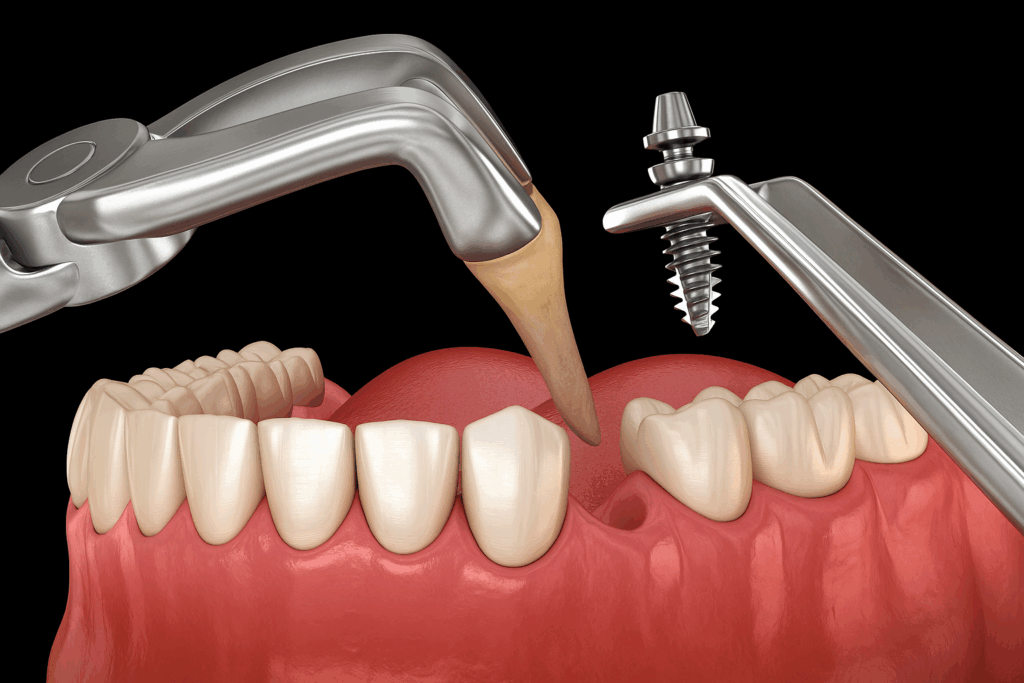

이를 해결할 수 있는 진료 방식이

‘발치 즉시 식립’이 될 수 있습니다.

민락 치과 에서 설명해 보자면

말 그대로 치아를 뽑은 그 자리에서

곧바로 픽스처를 심는 방식으로,

별도의 회복 기간을 두지 않고

다음 진료 단계로 넘어갈 수 있어

전체 기간을 단축할 수 있습니다.

동시에 발치 이후 흔히 나타나는

치조골의 흡수도 방지할 수 있는 점에서

많은 장점이 있는 술식이죠.